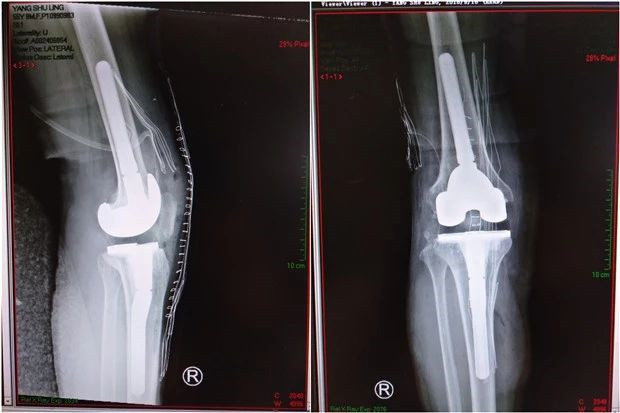

膝关节LCCK术后